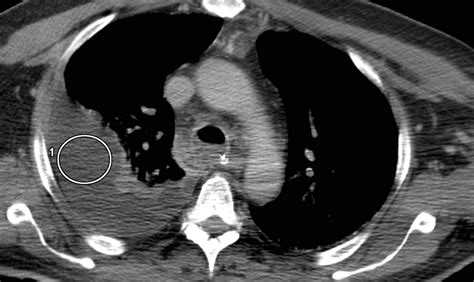

A Lung CT scan (computed tomography) is a sophisticated medical imaging procedure that provides detailed, cross-sectional images of your lungs, airways, and surrounding structures. By utilizing specialized X-ray equipment combined with advanced computer processing, it creates far more comprehensive images than a standard chest X-ray. If your healthcare provider has ordered this scan, it is likely to investigate unexplained symptoms, monitor existing conditions, or screen for specific risks. Understanding what to expect during this process can alleviate anxiety and help you feel prepared for your appointment.

Physicians utilize lung CT scans to diagnose, evaluate, and monitor a wide variety of respiratory issues. Because the scan provides high-resolution, 3D images, it is essential for identifying abnormalities that might be missed by traditional 2D imaging. Some common reasons for undergoing a scan include:

• Evaluation of Masses: Distinguishing between benign and malignant nodules or other lung lesions.